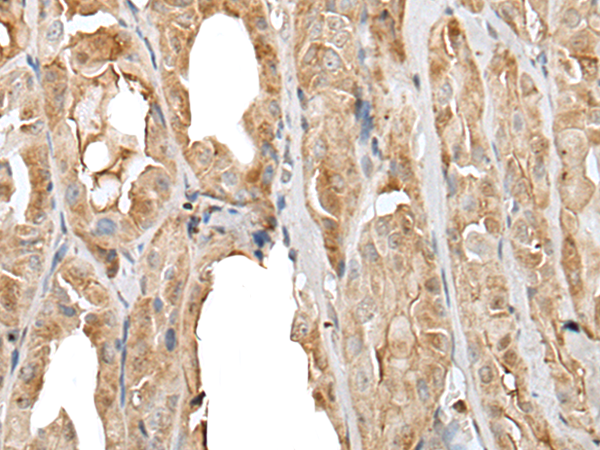

IHC positive control:

Human brain and human breast cancer

IHC Recommend dilution:

25-100